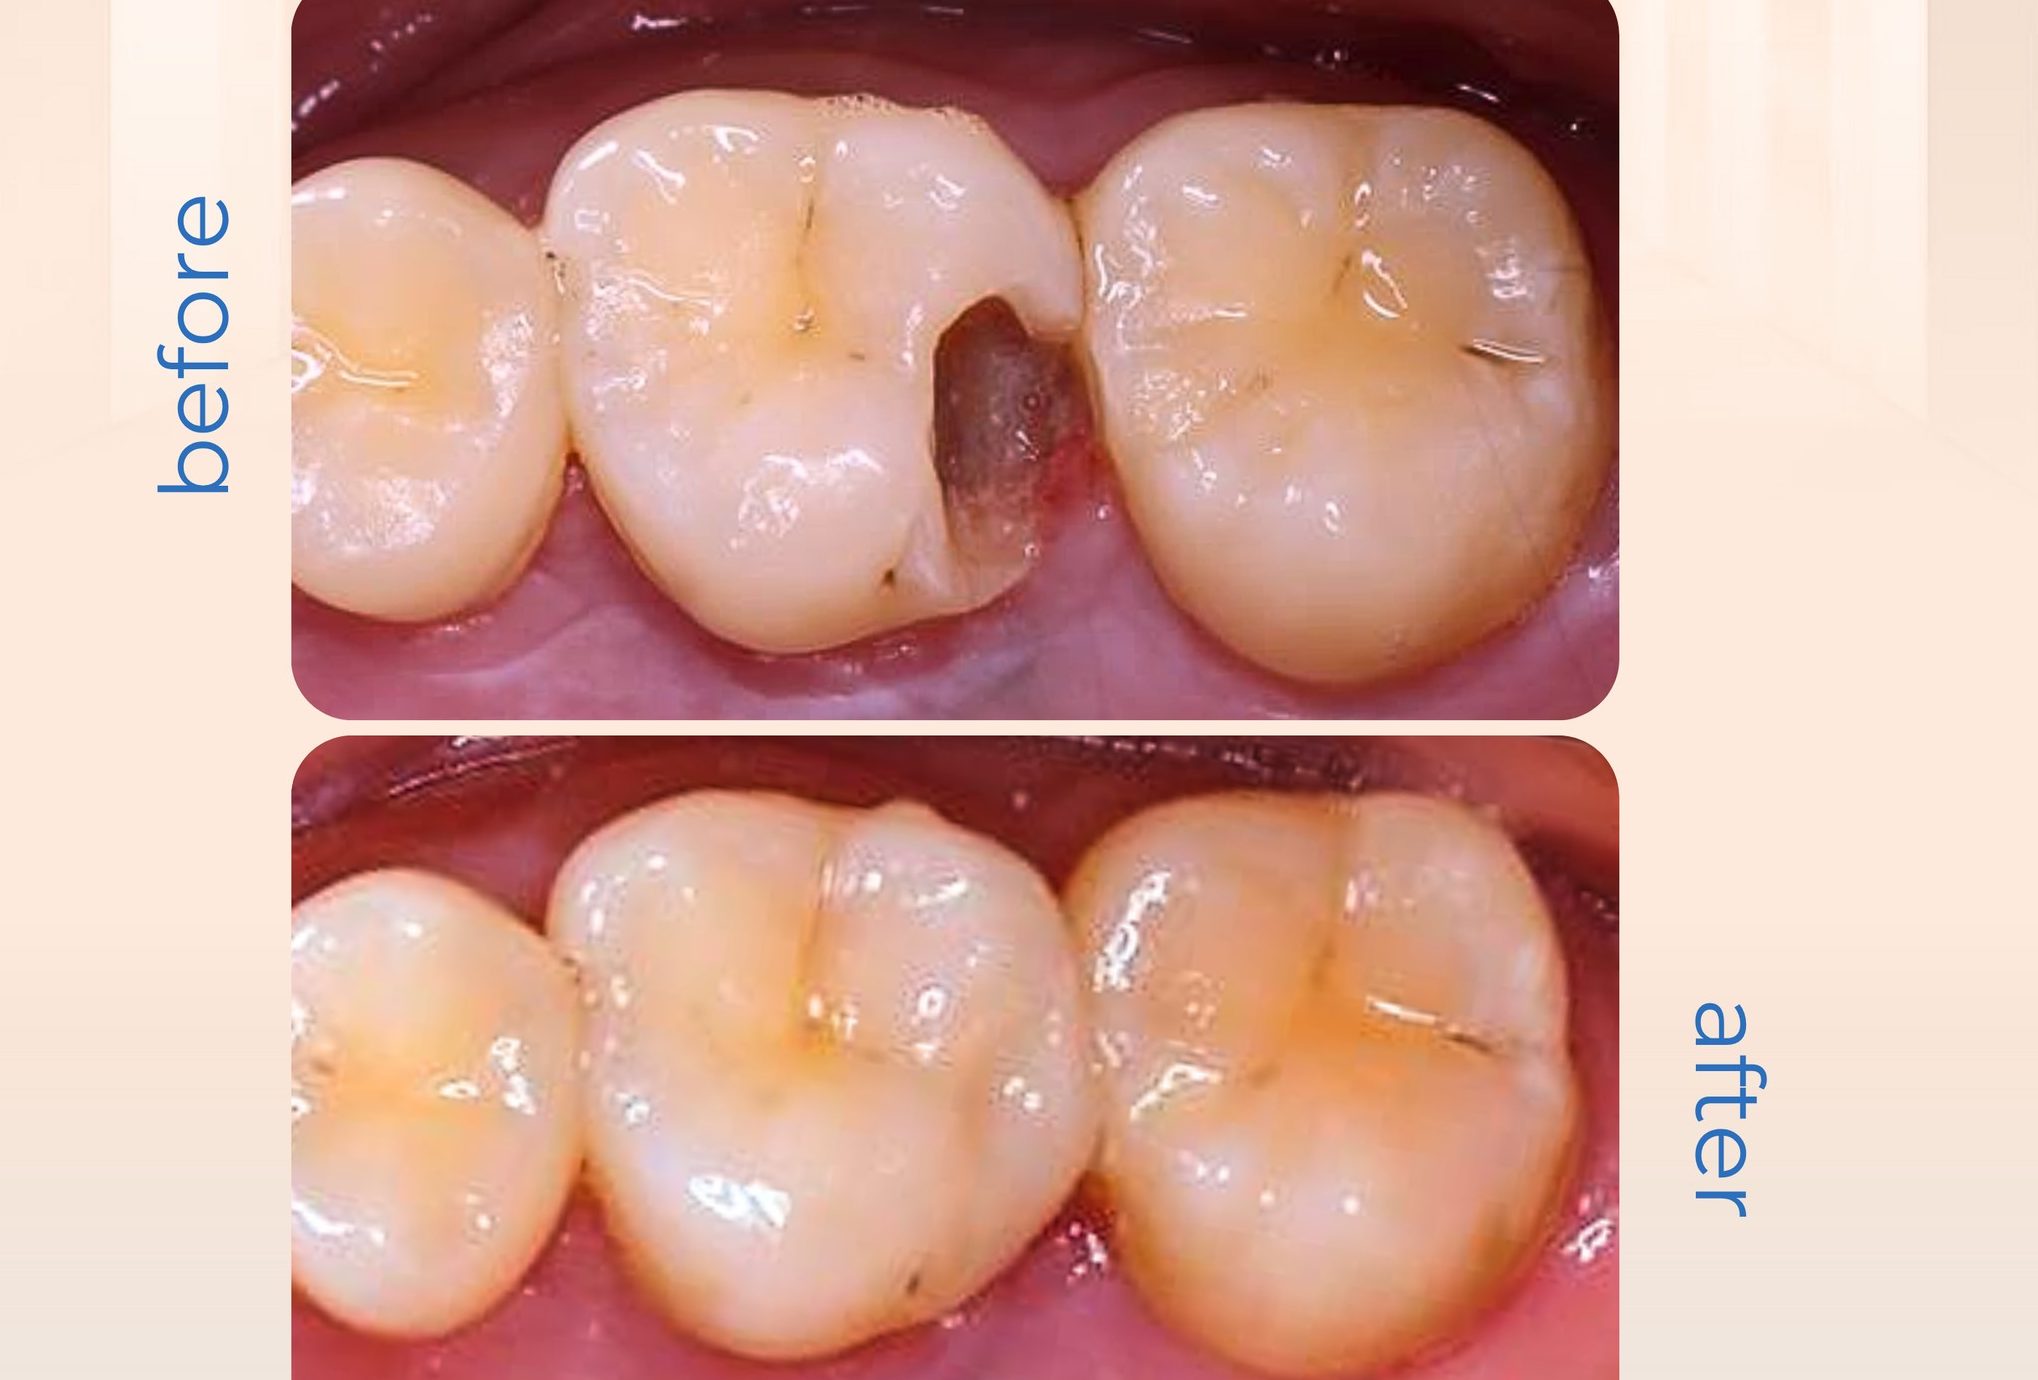

Hình Ảnh Trước & Sau Điều Trị

Minh chứng rõ ràng cho chất lượng và hiệu quả tại Nha khoa Như Ngọc – nơi mỗi khách hàng đều tìm lại được nụ cười tự tin sau quá trình điều trị và thẩm mỹ răng